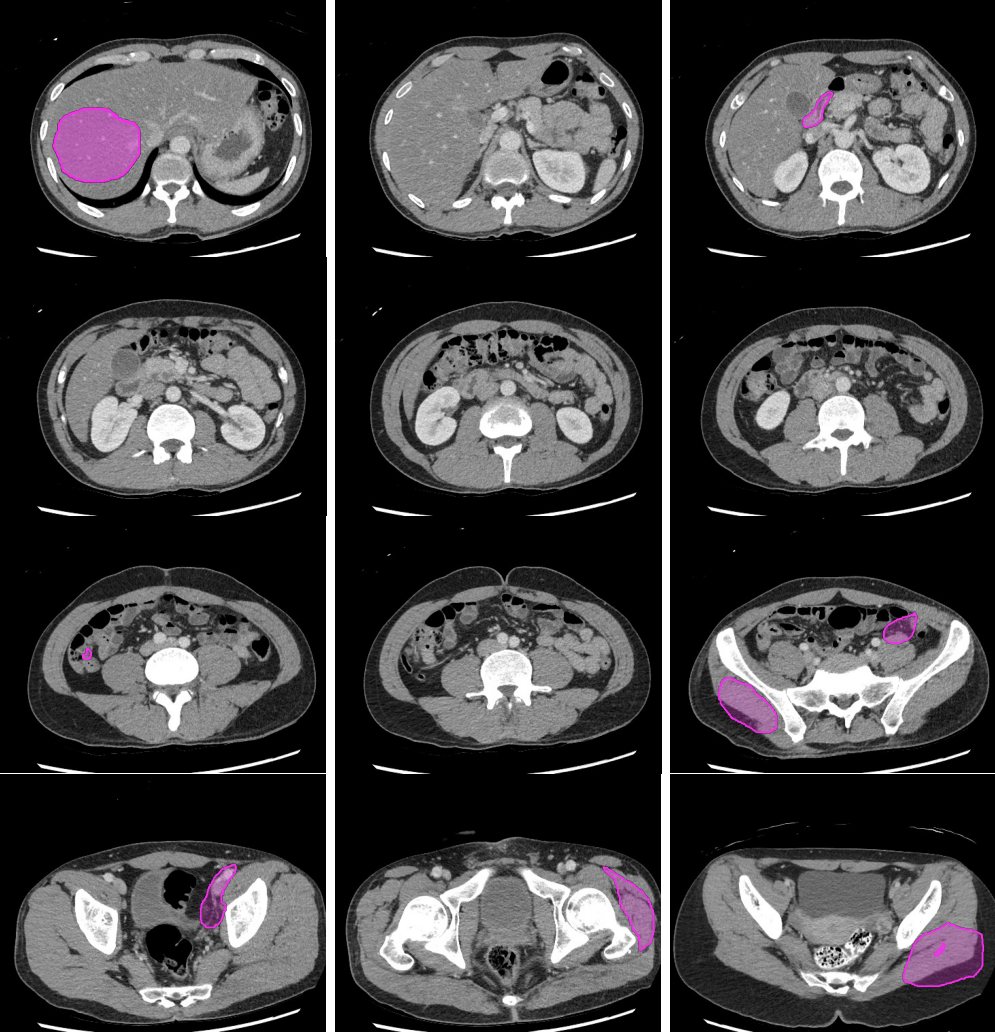

Legend

Slice 1

Slice 2

Slice 3

Slice 4

Slice 5

Slice 6

Slice 7

Slice 8

Slice 9

Slice 10

Slice 11

Slice 12